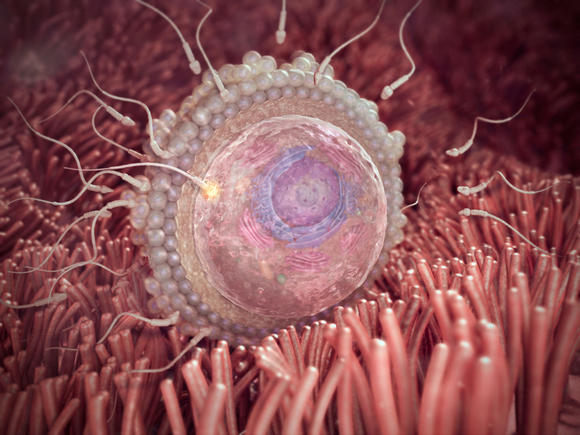

1-2 வாரம்

ஆணின் (தந்தையின்) விந்து (sperm) பெண்னின் (தாயின்) முட்டையோடு சேரும் தருணத்தில் ஒரு உயிர் கருத்தரிக்கிறது. கருத்தரித்த இந்த உயிர் தாயினின்றும் தந்தையினின்றும் முழுவதுமாக வேறுபட்ட தனித்தன்மை வாய்ந்த DNA கொண்ட தனி உயிர்.